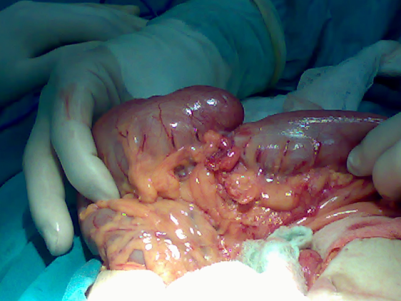

Crohn xəstəliyində intraoperativ nələr tapılır?

Nazik bağırsaqlarda divar qalınlaşması, “piy manjeti” (müsariqənin enterin antimezenterik divara doğru, irəliləməsi), qalınlaşmış və qısalmış mezenterium, fistul, abses